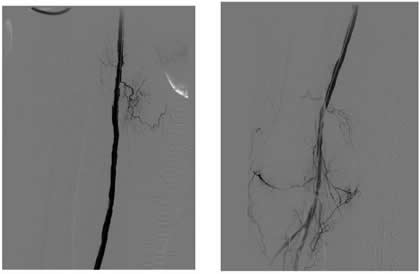

Case 1: An 84-year-old male with rest pain, who had undergone prior revascularization with covered stents, represents with recurrent rest pain. The prior stents had come close to the origin of the SFA and at that time there had been some narrowing. Exposure was provided by performing a cut down and patching the CFA-proximal SFA to the level of the stents, following which gentle thrombectomy was performed, and a wire passed down. The angiogram demonstrated a distal lesion at the adductor canal which contributed to the thrombosis (Figure 1A). The patient underwent a day of lysis, following which cryoablation was used to treat the distal lesion (Figure 1B) and completion angiogram showed restoration of limb perfusion (Figure 1C).